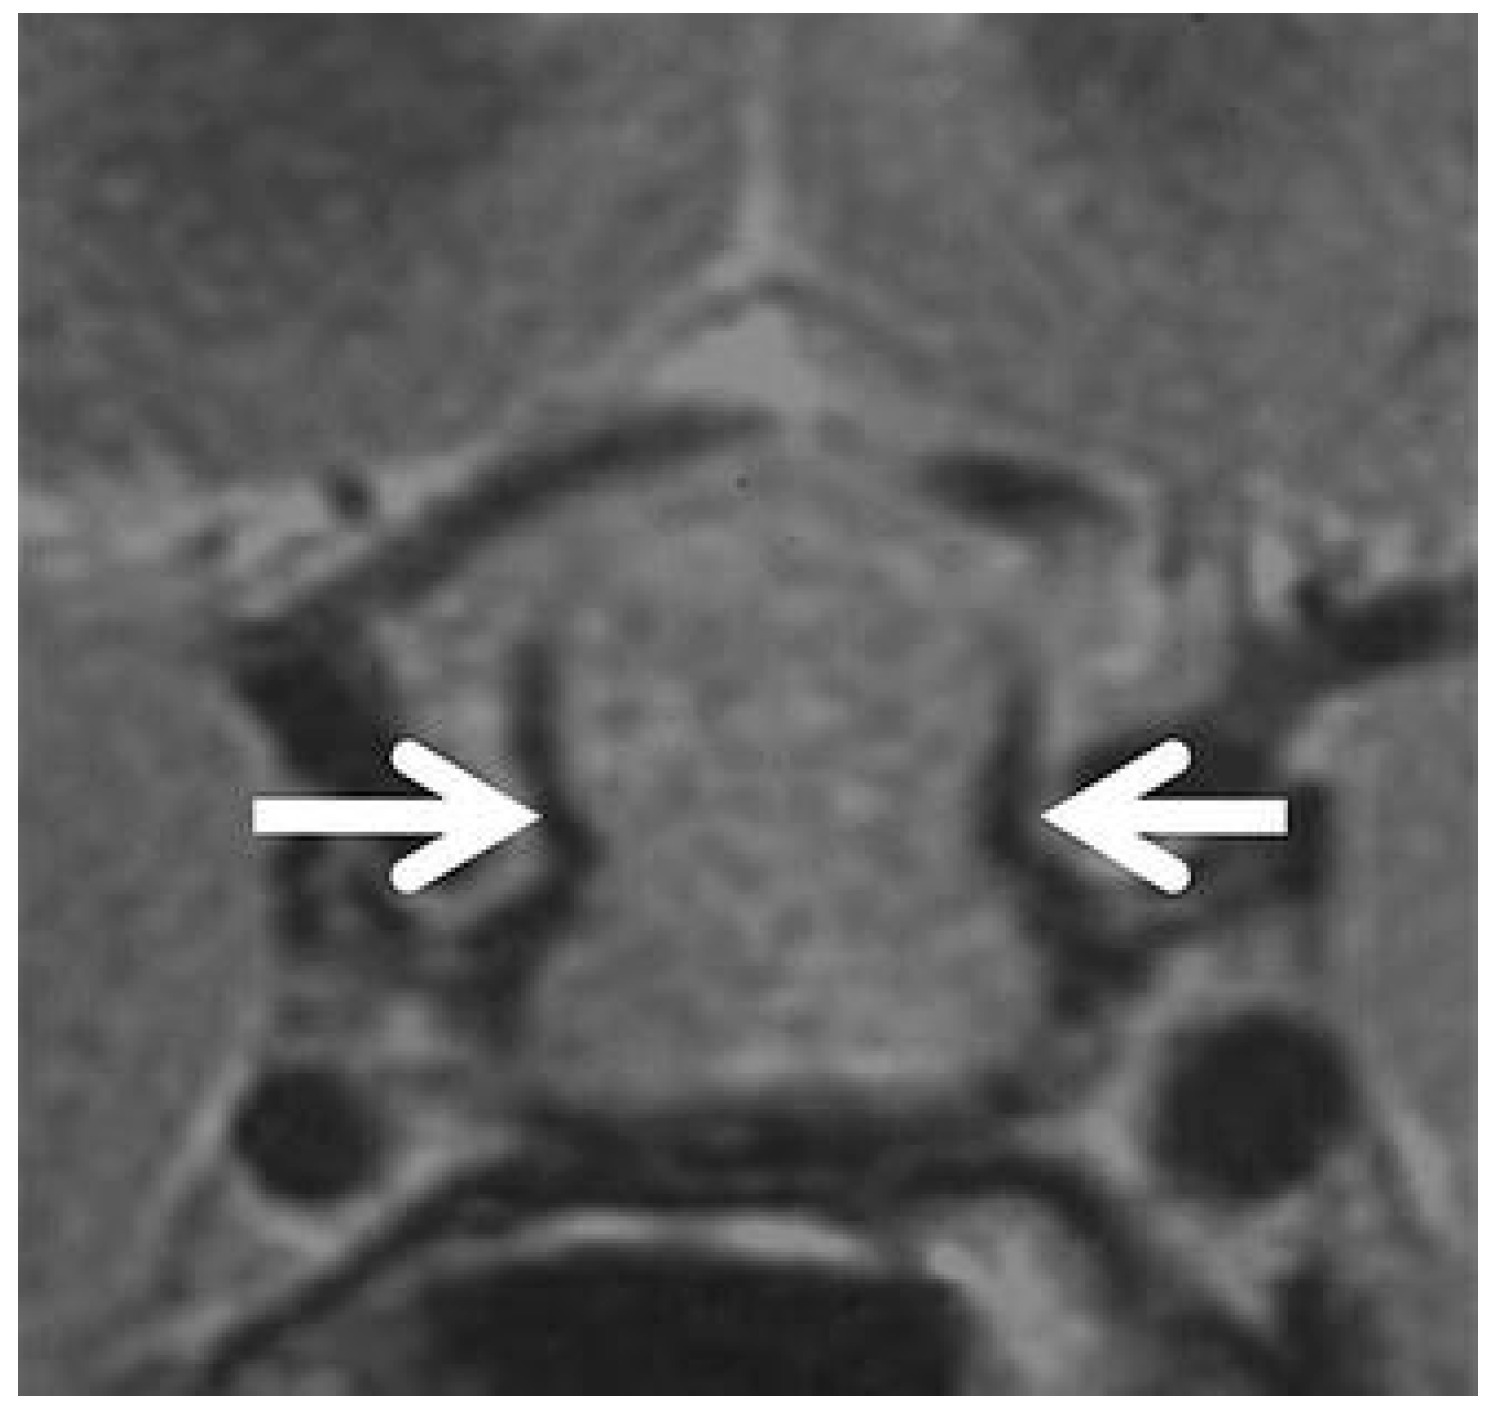

Several ancillary signs have also been described. Ectopic ADH storage is primarily observed in large NFPMA [79], while the presence of a pituitary pseudocapsule is almost exclusive to adenomas [80]. The dural-tail sign, although occasionally observed [1,3], lacks specificity and has not been retained as a discriminative criterion. Sphenoidal mucosal thickening has been described as more frequent in NFPMA [37,38], though without statistical significance in the study of Ach et al. [39]. Finally, the “parasellar T2 dark sign”, first reported by Nakata et al. [81] and Agarwal et al. [82], corresponds to a peripheral T2 hypointensity highly specific for lymphocytic hypophysitis, possibly related to fibrotic inflammatory tissue (Figure 4). While signs like the parasellar T2 dark sign are promising for their reported specificity, their clinical utility is currently limited by variable reproducibility and a lack of large-scale, multicenter validation. Their presence can support a diagnosis of hypophysitis, but their absence cannot rule it out. This highlights a key limitation of conventional MRI: despite detailed morphologic analysis, significant overlap remains, and no single feature is pathognomonic.

Figure 4. Coronal T2-weighted image showing a peripheral hypointense rim surrounding the parasellar region (white arrows) in a patient with a sellar mass extending superiorly into the suprasellar cistern, consistent with hypophysitis [81].